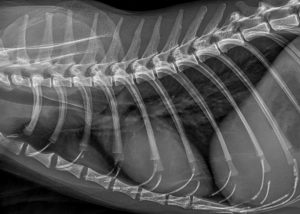

Die Indikation zum Röntgen ergibt sich aus verschiedenen Aufgabenstellungen heraus.

Bei z.B. Patienten mit Symptomen einer gemischten Dyspnoe oder Husten gilt es oftmals primär respiratorische von kardiologischen Ursachen abzugrenzen. Hierfür ist die Röntgenuntersuchung ein ideales Hilfsmittel. Die Folgen des Herzversagens sind röntgenologisch sehr gut darstellbar. Wir bekommen einen Hinweis auf den Grad der kongestiven Herzinsuffizienz (Stauungsherzinsuffizienz mit Stauung der Gefäße, Lungenödem oder Thoraxerguß) und auch der Therapieverlauf ist sehr gut zu kontrollieren. Beide bildgebenden Verfahren sind komplementär anzuwenden. Die genaue Diagnose der Art der Herzerkrankung und damit der Grundlage jeglicher Therapie bleibt sicher nur der Echokardiographie vorbehalten.